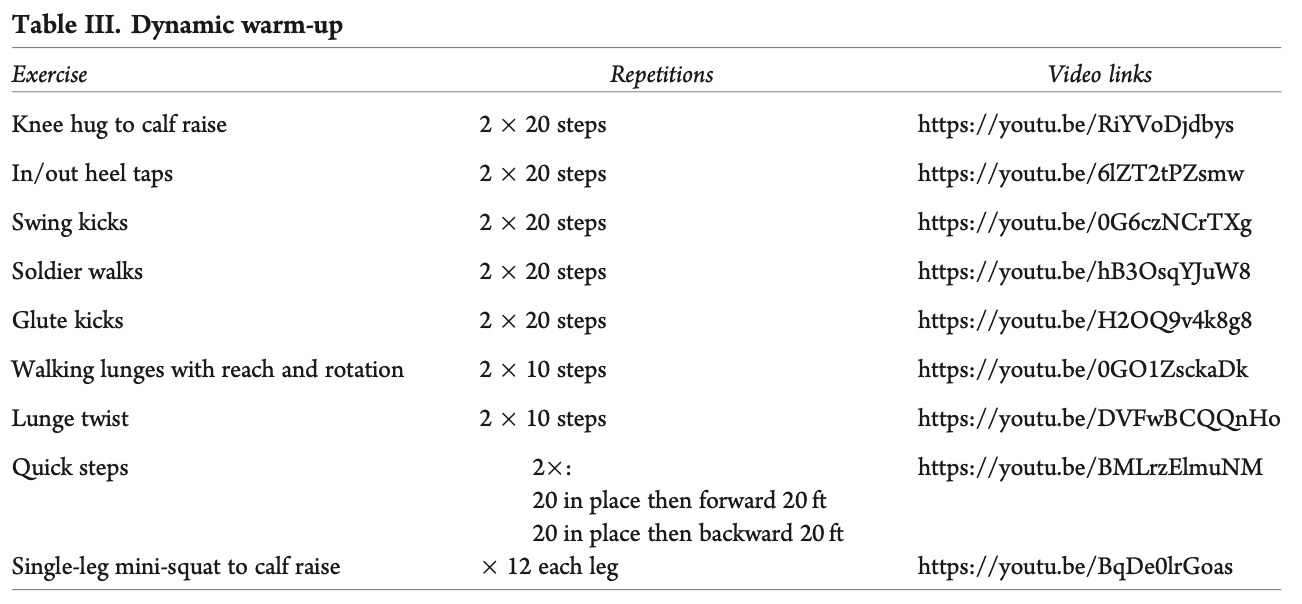

每次锻炼或跑步前,都需要进行动态热身,包括以下练习。 (A)抱膝至小腿抬高,(B)脚跟内/外拍打,(C)摆动踢,(D)士兵走,(E)臀部踢,(F)带伸展和旋转的步行弓步,(G)弓步扭转,(H)快步,以及(I)单腿迷你深蹲至小腿抬高。